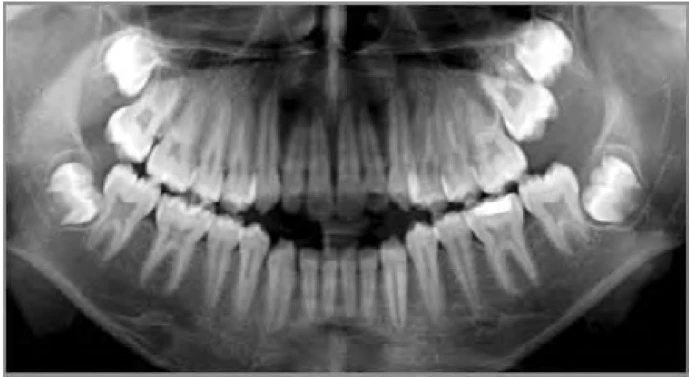

Hình 9D. Mũi tên đen chỉ vào răng nanh hàm dưới hoàn toàn nằm ngoài cung hàm và có thể bị nhổ bỏ như là một phần của kế hoạch điều trị chỉnh nha, mũi tên trắng chỉ vào một răng cối nhỏ thứ hai hàm trên bị sâu răng nghiêm trọng

Hình 9F. Mũi tên đen chỉ răng cối lớn thứ nhất hàm dưới được chỉ định nhổ vì tình trạng nha chu

Hình 9G. Răng cối lớn thứ nhất hàm trên bên phải bị sâu nghiêm trọng được chỉ định nhổ